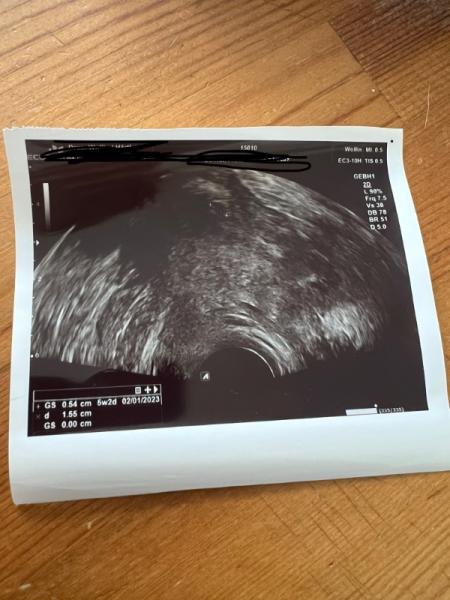

Hallo bin mir mega unsicher war heute beim Frauenarzt sie war sich auch noch nicht sicher ob da was ist habe leider davor 2 Abgänge gehabt Bin jetzt in der 5+2 laut Frauenarzt

Bild zu Ist das eine Fruchthöhle oder nicht - Kinderwunsch - was tun, um schwanger zu werden?

Meiner Meinung nach sollte die Gebärmutter viel weiter unten im Bild sein, aber die ist da gar nicht gut zu erkennen. Wie weit sollst du denn laut deiner Rechnung sein?

5+2 laut ihren Rechner